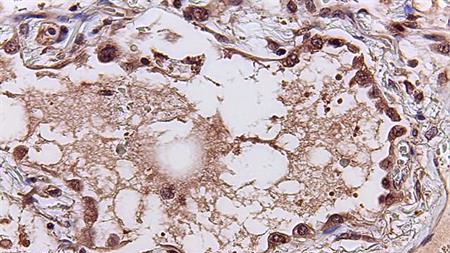

Two telltale signatures emerged from the study, published in eBiomedicine. One, a set of 166 genes, reveals how the human immune system responds to viral infections. A second set of 20 signature genes predicts the severity of a patient’s disease. For example, the need to hospitalize or use a mechanical ventilator. The algorithm’s utility was validated using lung tissues collected at autopsies from deceased patients with COVID-19 and animal models of the infection.

By examining the source and function of those genes in the first signature gene set, the study also revealed the source of cytokine storms: the cells lining lung airways and white blood cells known as macrophages and T cells. In addition, the results illuminated the consequences of the storm: damage to those same lung airway cells and natural killer cells, a specialized immune cell that kills virus-infected cells.